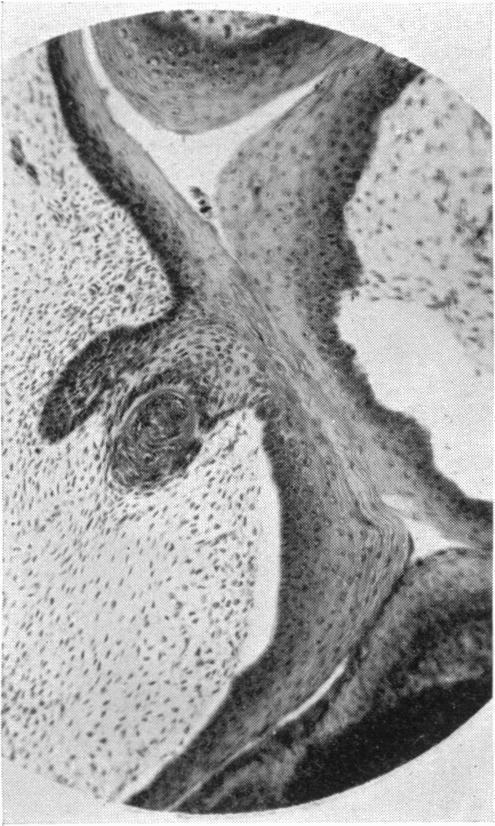

Green H L

University of Cambridge.

J Anat. 1930 Jul;64(Pt 4):512-522.1.